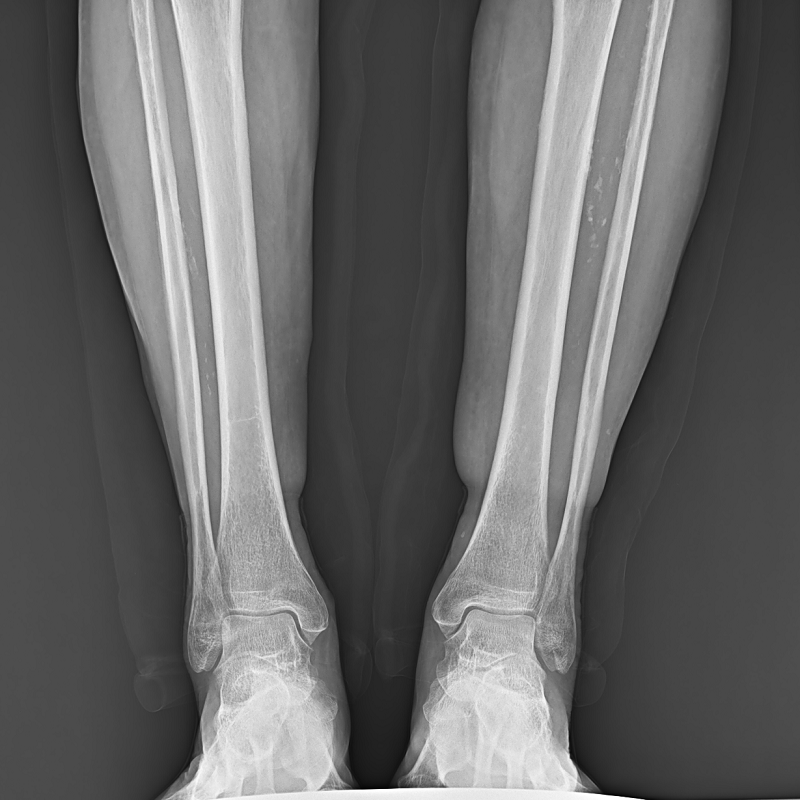

全自動(dòng)拼接

●呈現(xiàn)全下肢或全脊柱圖像

●在脊柱及下肢畸形矯正手術(shù)治療中,為術(shù)前方案制定和術(shù)后復(fù)查提供精準(zhǔn)測(cè)量

●有效解決傳統(tǒng)X光片不能一次成像問題,為患者提供更加優(yōu)質(zhì)的醫(yī)療服務(wù)

Clinical picture

臨床圖片